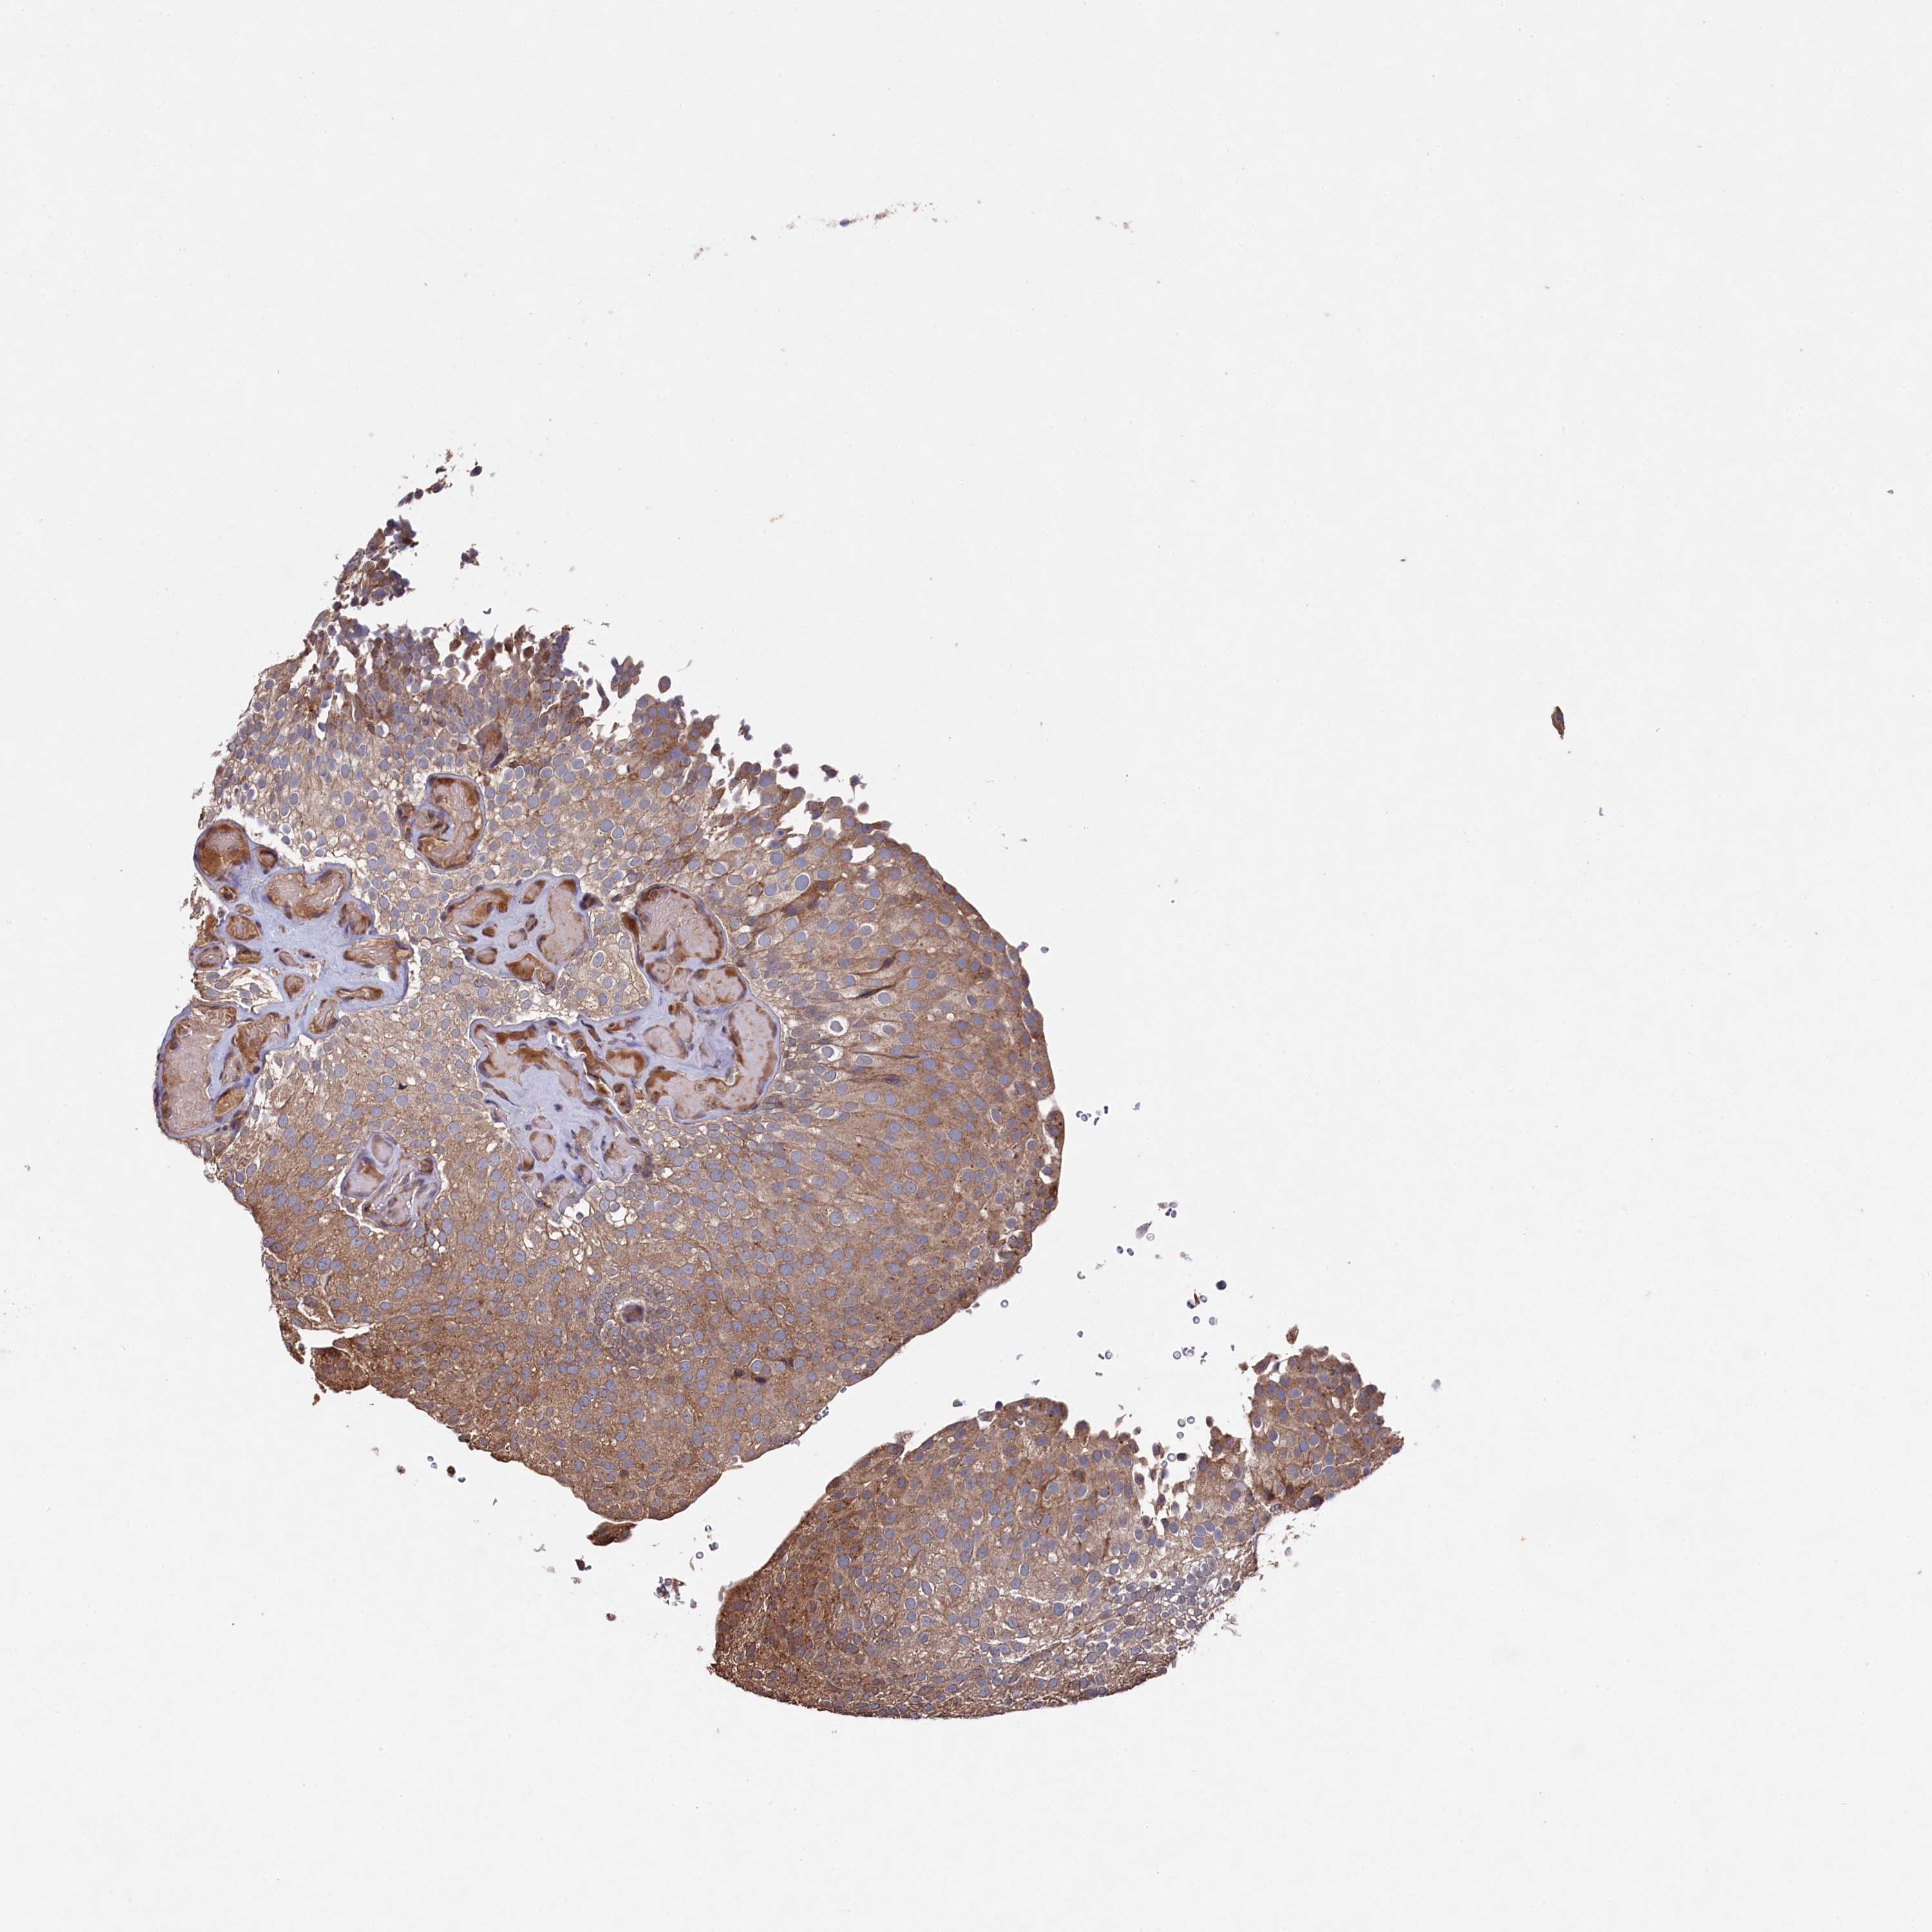

UROTHELIAL CANCER - Protein expressioni

A mouse-over function shows sample information and annotation data. Click on an image to view it in a full screen mode. Samples can be filtered based on level of antibody staining by selecting one or several of the following categories: high, medium, low and not detected. The assay and annotation is described here.

Note that samples used for immunohistochemistry by the Human Protein Atlas do not correspond to samples in the TCGA dataset.

Antibody stainingi

Antibody staining in the annotated cell types in the current human tissue is reported as not detected, low, medium, or high, based on conventional immunohistochemistry profiling in selected tissues. This score is based on the combination of the staining intensity and fraction of stained cells.

Each image is clickable and will lead to virtual microscopy that enables deeper exploration of all samples and also displays staining intensity scores, fraction scores and subcellular localization as well as patient and tissue information for each sample.

Antibody HPA040916

Staining

High

Medium

Low

Not detected

Intensity

Strong

Moderate

Weak

Negative

Quantity

>75%

75%-25%

<25%

None

Location

Nuclear

Cytoplasmic/membranous

Cytoplasmic/membranous,nuclear

Urothelial carcinoma, High grade